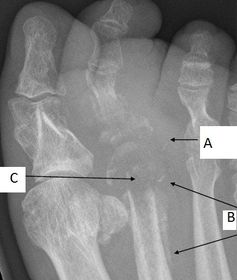

| What disease is this? What is shown by A, B and C? | Psoriatic arthritis. A = destructive changes B = Pencil in cup deformity C = IPJ fusion |

| What disease is this? | Psoriatic arthritis |